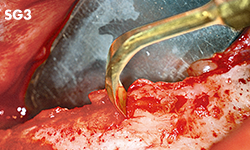

Ostroplasties

Unilateral anterior mandibular sampling

Excision of bone torus

Anterior mandibylar harvesting

Mandibular harvesting at approach stage

The cutting part is bone torus